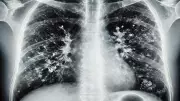

Zatürre Uyarısı: Öksürüğü Hafife Almayın

Göğüs Hastalıkları Uzmanı Dr. Mustafa Kemal Kaya, zatürrenin soğuk algınlığı ile karıştırılmaması gerektiğini vurguladı. Erken tanı ve aşı ile korunma hayati önem taşıyor.